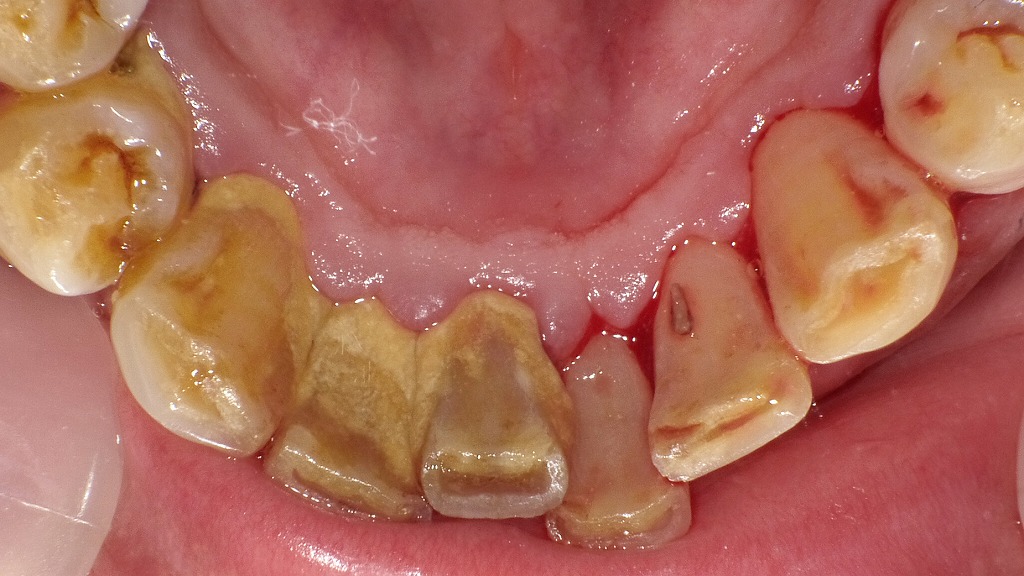

この写真では、複数の要因が重なり合い、**歯が浮くような違和感(歯が押される・浮いた感じ・噛みにくい感じ)**が起こりやすい状態が確認されます。

① 歯ぐきの腫れ(歯肉炎・歯周病のサイン)

歯ぐきが全体的に赤く腫れ、丸く盛り上がった状態で、強い炎症が起きています。

歯周病が進むと、炎症によって歯ぐき内部の血流が増え、歯が浮き上がるような感覚が生じます。

② 歯周病による歯の支持力低下

歯と骨の間の歯周組織が炎症でダメージを受けると、

・噛むと響く

・浮いた感じがする

・当たると痛い

といった症状が出やすくなります。

③ 歯面の広範囲にみられる歯垢(プラーク)と歯石

歯と歯ぐきの境目、特に前歯の間や側方部に黄色〜茶色の歯垢・歯石が強く付着しています。

これらは歯周病菌の温床となり、炎症をさらに増悪させます。

④虫歯の存在(痛みや浮遊感の原因に)

いくつかの歯には表面が溶けた虫歯が見られ、

炎症性の刺激によって歯の内部圧が上昇し、「浮く」感覚を強める場合があります。

◆ 総合評価

この写真では

歯ぐきの強い腫れ+歯周病の進行+歯垢・歯石の大量沈着+虫歯

という複合的な問題が重なり、「歯が浮く」症状が起きやすい典型的な状態です。

この段階ではセルフケアだけでは改善が難しく、

歯科医院での歯石除去、歯周治療、虫歯治療が必須となります。